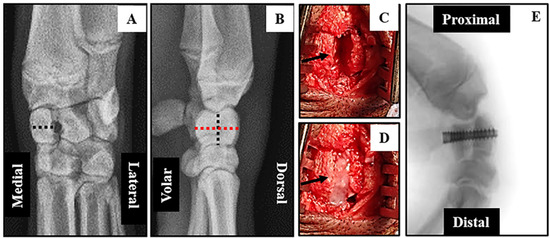

High resolution X-rays taken pre-operatively were used to confirm the dimensions of each radiocarpal bone prior to surgical intervention, and post-operative to ensure adequate fixation of the defect (Figure 2).

Figure 2.

Surgical intervention to generate radiocarpal non-union: X-rays of the forearms of anesthetized mini-pigs were obtained in the coronal (A) and sagittal (B) planes to measure the dimensions (dotted lines) of the radiocarpal bones prior to surgery. Medial-Lateral = 7.4 mm; Volar-Dorsal = 17.5 mm and Proximal-Distal 10.5 mm. 3 mm osteotomies (C arrow) were performed through the mid-radiocarpal bone of both forelimbs. The volar and dorsal pieces of the LEFT radiocarpal (control) were fixed immediately and a dense-collagen spacer (D arrow) inserted in the gap of the RIGHT radiocarpal (non-union). After 7 weeks of healing the LEFT radiocarpal had no further intervention while the spacer in the RIGHT radiocarpal was removed, the volar and dorsal segments re-apposed and fixed with a screw (E). The mini-pigs were left for an addition 12 weeks before termination of the experiment.

The time taken to anesthetize the animals and perform bilateral surgical interventions on each of three mini-pigs varied between 80 min and 110 min. Surgeries were uneventful except for a partial fracture of the volar aspect of the left radiocarpal at the time of screw insertion in the first animal operated. This bone was subsequently excluded from all post-mortem analyses leaving only two animals for direct comparison of bone repair after immediate fixation (IF) and three for delayed fixation (DF). All mini-pigs were fully ambulatory within 48 hours post-operation and had no visible signs of infection or other complications after one week. Micro CT and un-decalcified histological analyses (Figure 3) clearly demonstrated mal-union of the right radiocarpal bone at 19 weeks post-operative. The dorsal and volar segments were rigidly fixed at seven weeks after removal of the dense collagen spacer.